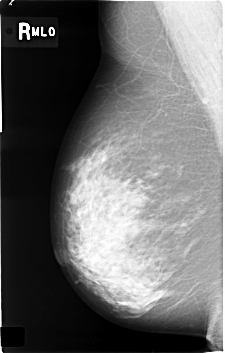

C_0362_1.RIGHT_MLO

RIGHT_CC LINES 4584 PIXELS_PER_LINE 2920 BITS_PER_PIXEL 12 RESOLUTION 50 NON_OVERLAY

RIGHT_MLO LINES 4584 PIXELS_PER_LINE 2920 BITS_PER_PIXEL 12 RESOLUTION 50 NON_OVERLAY